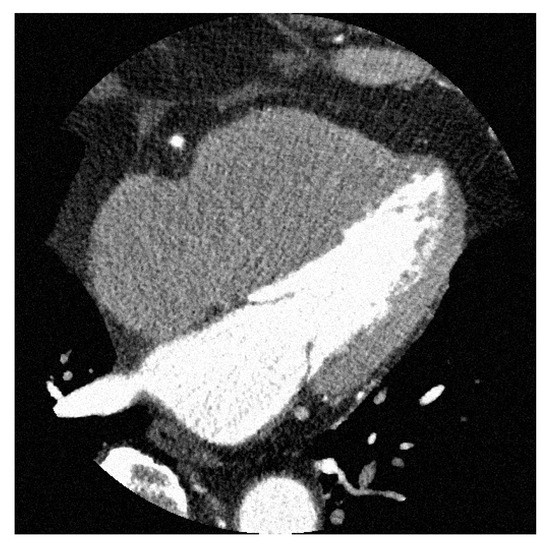

3.2. SVD Using CCTA